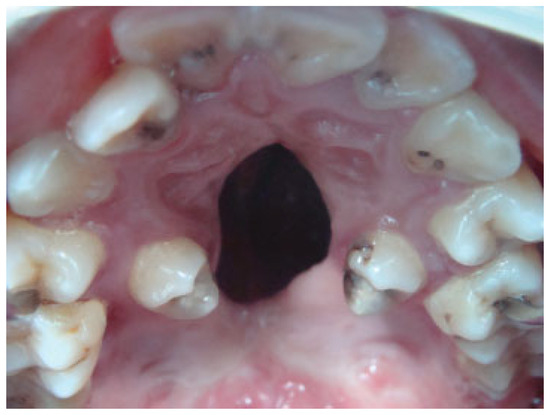

Palatal fistula is a difficult complication after cleft palate repair. The repair of a palatal fistula can be challenging, particularly in wide and recurrent fistulas (Figure 1). Large defects after cleft palate repair produce various symptoms, including regurgitation of fluid into the nasal cavity, hearing loss, and velopharyngeal insufficiency. In these cases, the palatal tissue around the fistula can be quite scarred and in short supply. A variety of reconstructive options are commonly employed, using local flaps of muscle and mucosa or tongue tissue or using distant flaps [1,2,3]. The combination of buccal mucosal flaps and buccinator muscle as an axial myomucosal flap based on the facial artery has been described by Pribaz et al. [2].

Figure 1. Severe palatal fistula after primary palatoplasty in a 7-year-old patient.